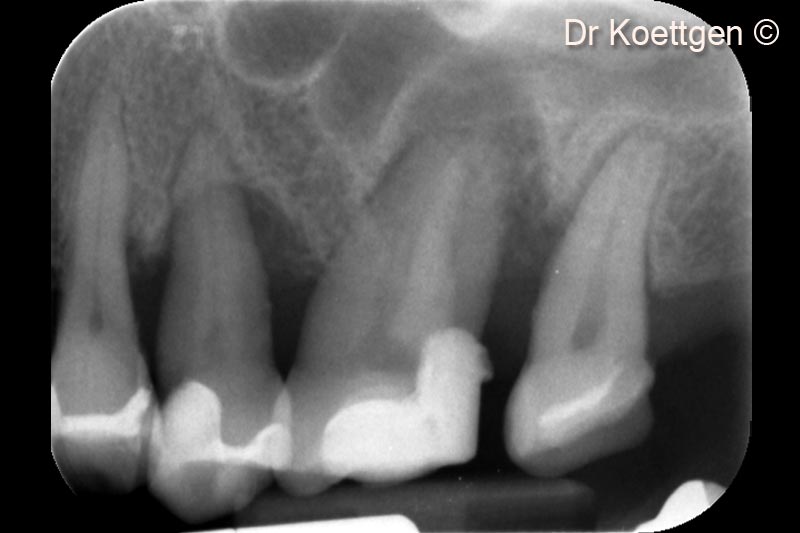

Sau khi nhổ răng, bệnh nhân nữ (63 tuổi) cần tăng cường mô cứng và mô mềm.